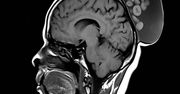

Guzy można łatwo zdiagnozować poprzez badanie USG - są na nich bardzo wyraźnie widoczne. Ich leczenie, w zależności od stopnia złośliwości, polega na wycięciu zmiany i zastosowaniu chemioterapii lub radioterapii. Metoda leczenia powinna być indywidualnie dobrana do rodzaju nowotworu i stanu zdrowia pacjenta.